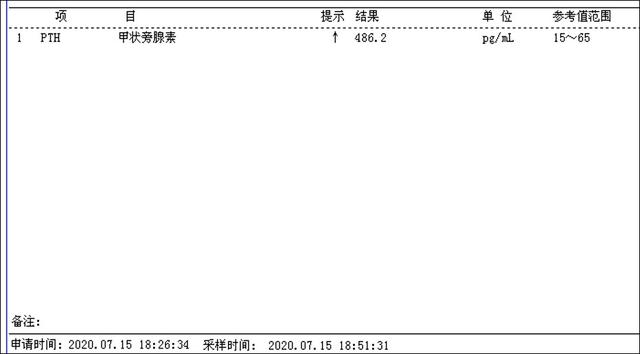

介入微创消融治疗后第一天甲状腺旁腺素降为486.2pg/ml(治疗前为3300pg/ml),静脉持续补钙血钙正常